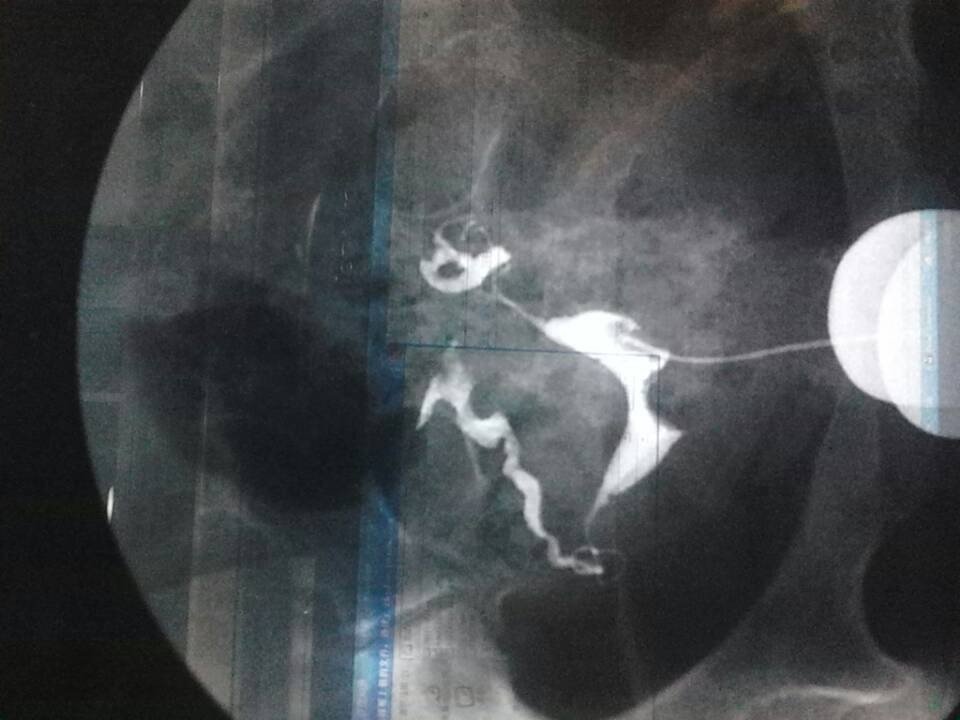

子宫输卵管造影结果是宫颈管通畅,子宫腔形态呈鞍型改变,大小未见异常 宫壁光整,未见充盈缺损及周围你 如影。 点击展开 匿名用户 2013-11-08 18:13 为您推荐: 其他回答 病情分析: 这个情况应该是有鞍状子宫的改变的,同时双侧输卵管表现还是符合通而不畅的。 指导意见: 鞍状子宫可能会影响怀孕的,但是也不一定,可以先尝试自己怀孕。如果经常中晚期流产的话,要处理子宫的。 匿名用户 2013-11-08 20:35 相关问题 子宫腔大小形态如常 未见充盈缺损两侧输卵管部分显示 盆腔内未见造影剂涂抹 上个月做了造影后输卵管通而不畅,盆腔粘连,还有宫颈糜烂中度,想问下怎么治疗啊 我和我男友同居一年都没怀孕,后来我到医院看,医生说,子宫,宫颈都很正常,输卵管有点不通畅,卵泡多一